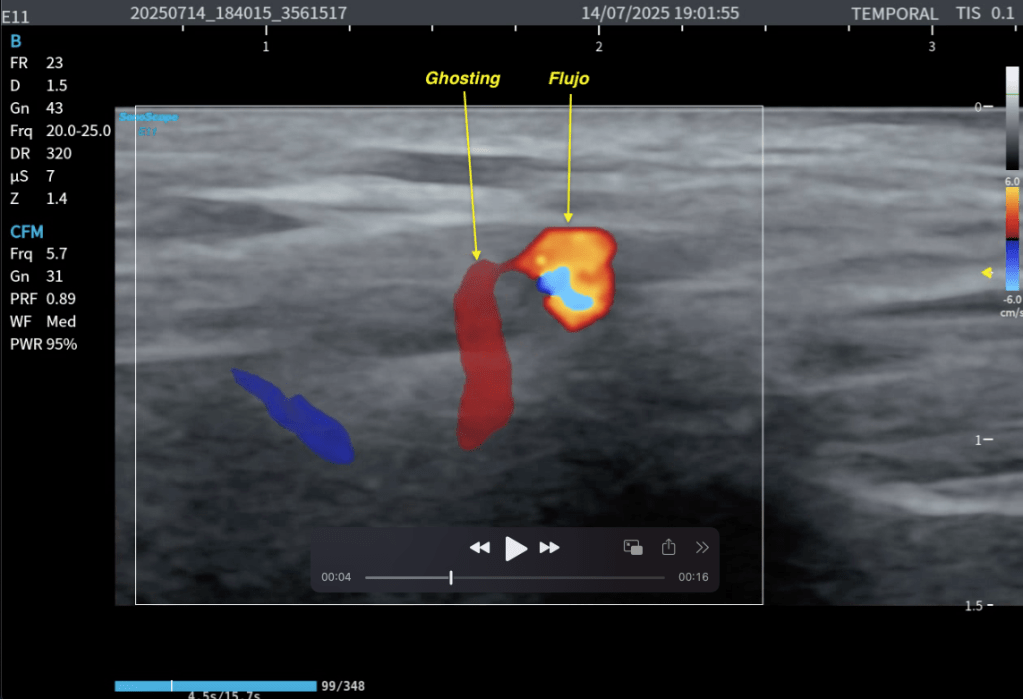

Mira el vídeo:

Ghosting

El ghosting Doppler se reconoce porque:

El vaso se mueve y el color va detrás, aparecen estelas de color, el flujo parece duplicado, el color se “despega” del vaso al barrer.